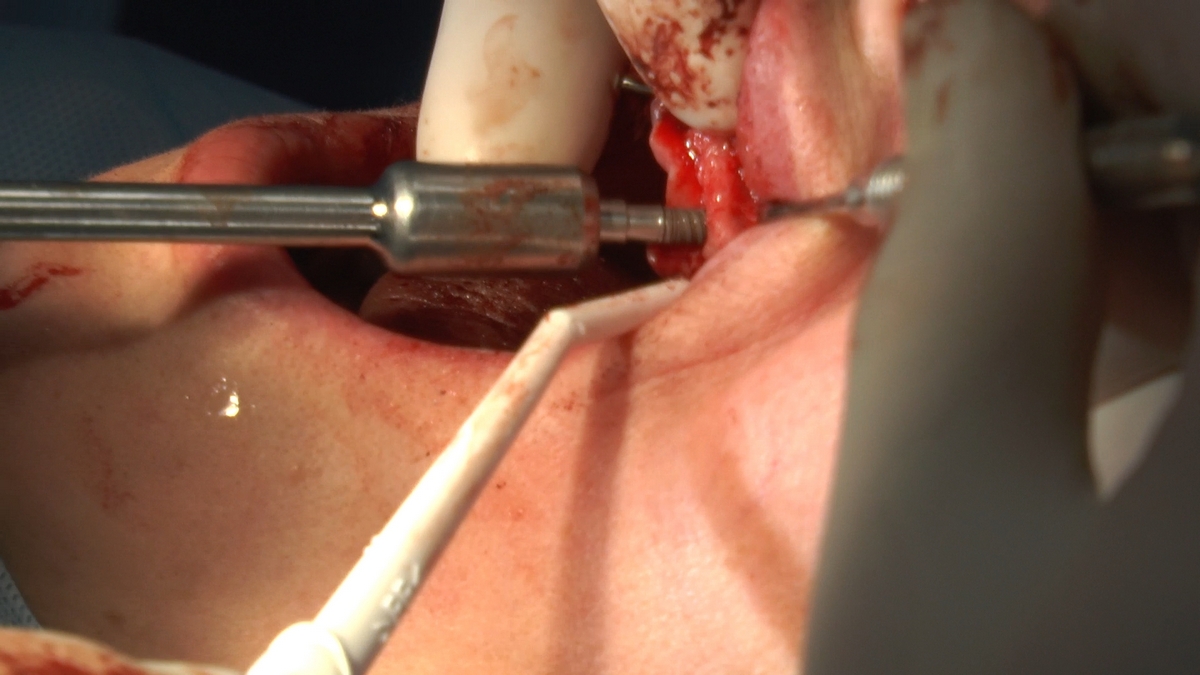

W trakcje dwóch dni zabiegowych, piątek i sobota, 5 i 6 października 2018 roku, lekarze uczestniczący w 6 Sesji VI Sezonu, wykonali wiele zabiegów o wysokim stopniu trudności. Przeprowadzili je pod kierunkiem Mentorów Instytutu Vivadental – dr n.med. Violetty Szycik, dr n.med. Magdaleny Kisłowskiej-Syryczyńskiej oraz dr Małgorzaty Piotrowskiej.

jeden zabieg sinus lift otwarty

zabiegi regeneracji kości z zastosowaniem materiałów kościozastępczych i kości własnej oraz fibryny bogatopłytkowej,